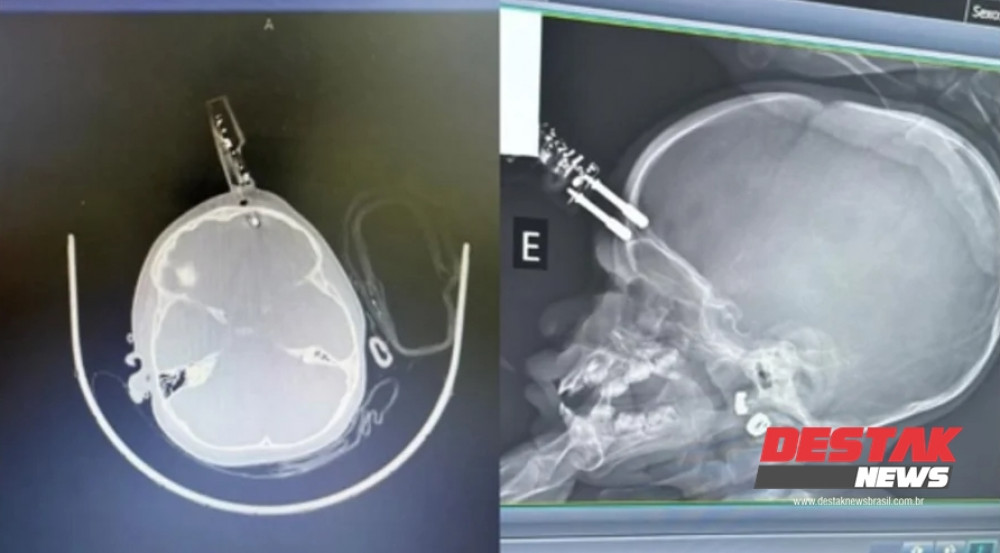

DIVINÓPOLIS (MG) – Um acidente doméstico mobilizou equipes médicas e gerou grande apreensão em Divinópolis na última terça-feira (13). Uma menina de apenas 1 ano de idade precisou ser submetida a uma intervenção cirúrgica de urgência após cair da cama e ter os pinos de um carregador de celular cravados em sua testa.

Segundo o relato do neurocirurgião Dr. Bruno Castro, responsável pelo atendimento, o acidente ocorreu em um breve momento de distração. A mãe da criança teria se ausentado por poucos instantes para ir ao banheiro. A pequena, que segurava o carregador de celular na mão enquanto estava sobre a cama, acabou se desequilibrando e caindo. No impacto contra o solo, o objeto, que estava voltado para cima, penetrou profundamente na região frontal do crânio.

2. Retirada do Objeto: Realizada de forma controlada para evitar hemorragias ou danos a tecidos cerebrais.

3. Lavagem e Reconstrução: Após a retirada, foi feita uma limpeza interna profunda, o fechamento dos tecidos e a reconstrução estética e funcional da área atingida.